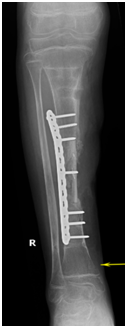

A13 y old boy previously healthy, sustained to gunshot injury, with segmental bone defect in the middle third of the right tibia and lose of soft tissue, Initial irrigation and debridement with fixation of the tibia by external fixator were done in the peripheral hospital, Five weeks later the patient was transferred to our institute (level I trauma center) for definitive management. On examination we found a 4x6 cm wound at the anteromedial aspect of the right tibia (Figurs1a & 2b), with foot drop. X-ray revealed mid-shaft fracture of the tibia with bone loss of about 6 cm (Figure 2a & 2b).

• Figure 2a & b AP and Lateral leg x-rays demonstrating the bone defect.

Three month later, the external fixator was removed; back slab was applied for 10 day to decrease the possibility of pin site infection. Final augmentation of the grafting was done by fibular allograft and fixed by 12 whole LCP. The nerve grafting performed (Figures 5a-5c). Two months later, the patient was seen in the clinic, he was able to move his ankle, radiography of the tibia demonstrated a remarkable filling of the gap by bone (Figures 6a-6d).

• Figure 5a-c During fixation of the tibia with DCP plate and insertion of fibular graft and grafton.